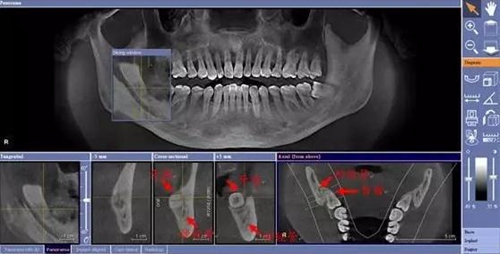

在比如智齒:

由于智齒的生長位置特殊,導(dǎo)致了拔除難易不同,如智齒出現(xiàn)橫著長或者靠近牙神經(jīng)的話,則難度會較高,一般人只需拍個口腔全景片,但相對于智齒靠近神經(jīng)管的情況,還可能需要拍CT,這都很考驗牙醫(yī)的技術(shù)。

5.jpg

下面這兩張圖,據(jù)說拔牙費時1.5小時,收費14000元。